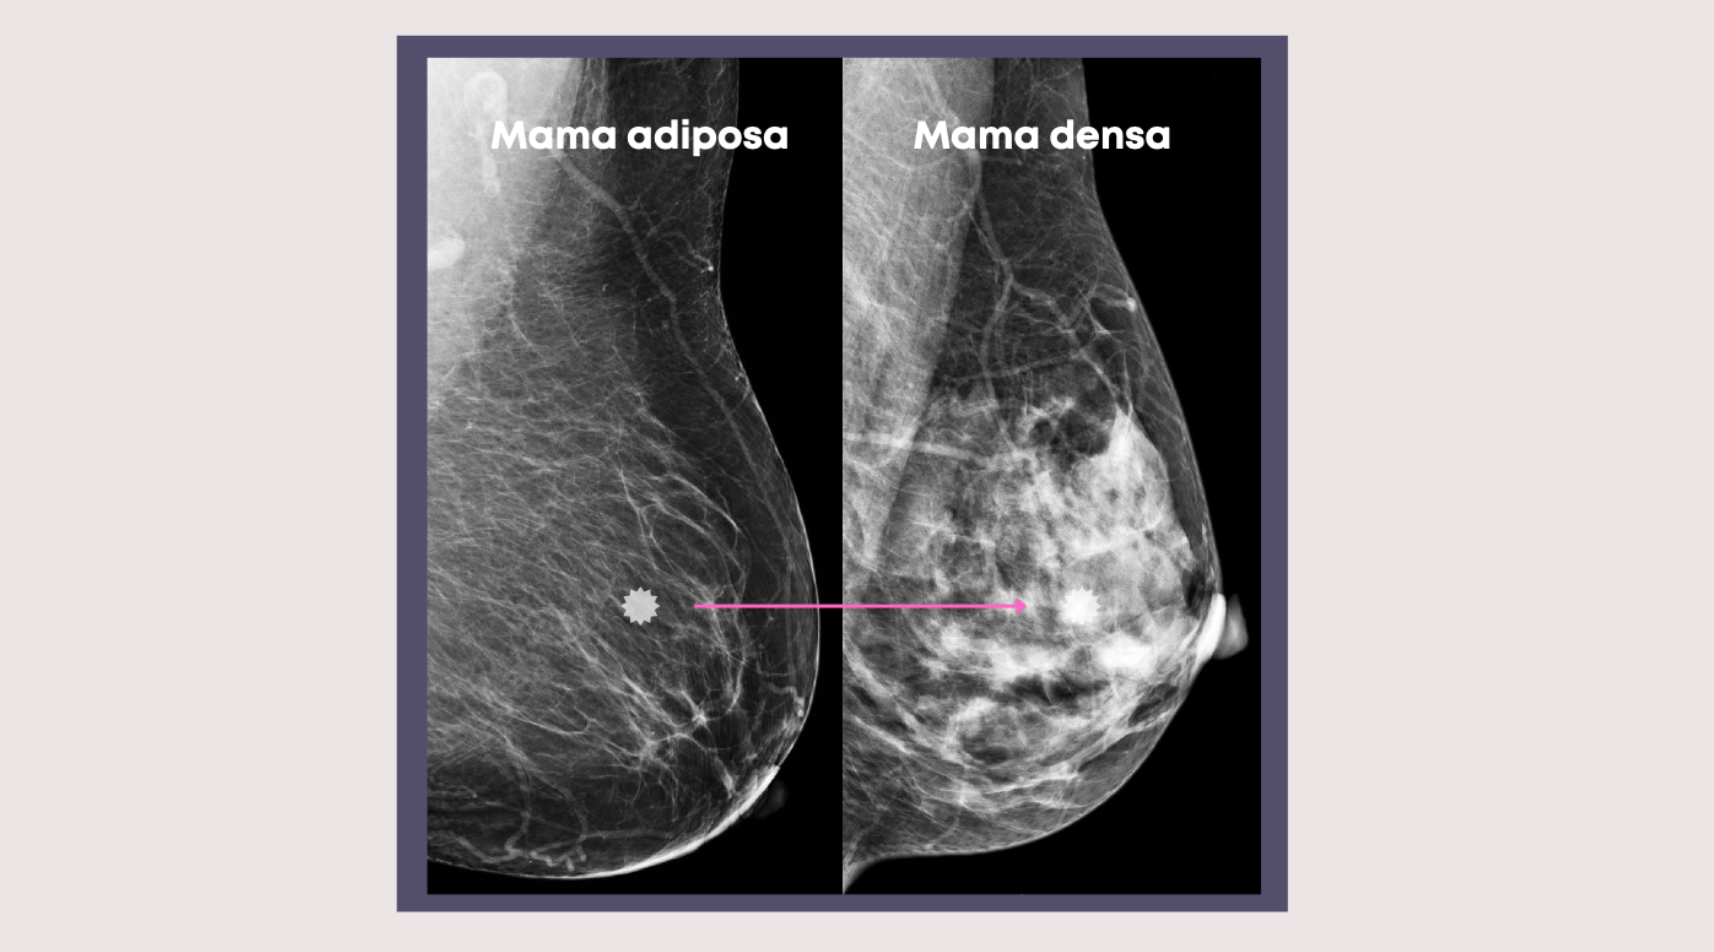

La densidad mamaria no se puede determinar a simple vista ni al tacto. Solo puede identificarse a través de una mamografía. En el informe de tu mamografía, el radiólogo clasifica la densidad mamaria en cuatro categorías, desde casi completamente grasa hasta extremadamente densa. Si tu informe menciona que tienes mamas densas, no te alarmes: es una condición común, pero sí requiere atención especial.

El tejido denso aparece blanco en la mamografía, al igual que los tumores, lo que puede ocultar lesiones pequeñas y dificultar el diagnóstico temprano. Encontrar un cáncer de mama pequeño en una mama densa es tan difícil como encontrar una pelota de golf en una tormenta de nieve. - Aumenta ligeramente el riesgo de cáncer de mama: